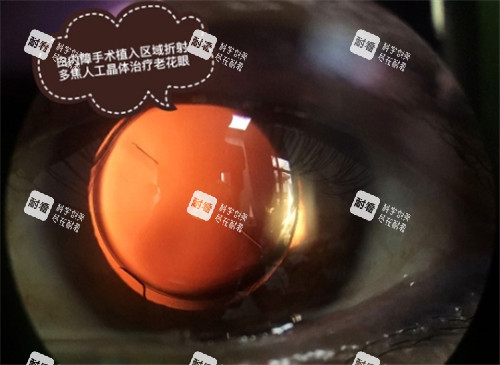

目前,手术是治疗白内障的主要方法,通过更换人工晶状体可以有效改善患者的视力。

白内障手术中使用的人工晶状体等材料也会影响报销。

一些高端的人工晶状体可能不在报销范围内,或者报销比例较低。

患者在选择手术材料时,需要与医生沟通,了解不同材料的报销情况,根据自己的经济状况和病情选择合适的材料。